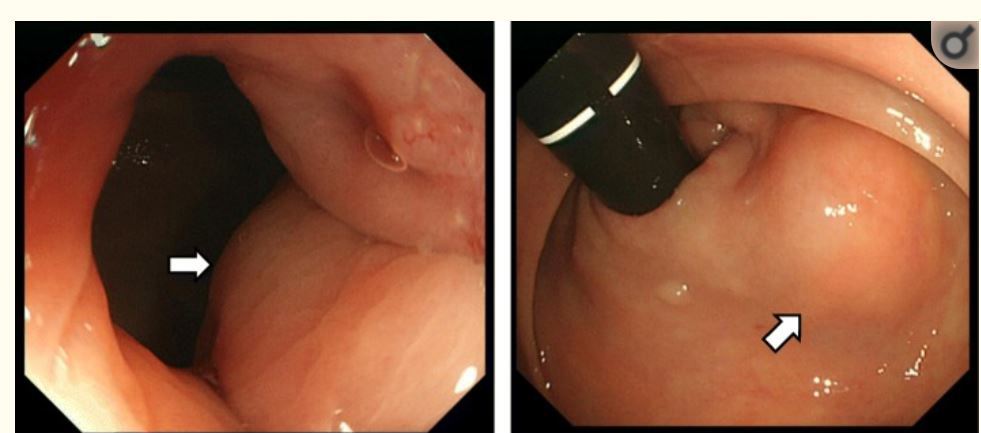

虫垂に発生したポリープ状の早期癌が内視鏡で見つかることが、あります。これは「通常の大腸癌と同じタイプが、たまたま虫垂に発生した」ものです(2020年 Review)。

虫垂早期癌の症例報告より

このような「解り易い」虫垂癌とは全く異なるタイプがあります。「虫垂粘液腫瘍=Appendiceal Mucinous Neoplasms (AMN)と呼ばれる独特な腫瘍は、病理学的には悪性度が高くないのに早期から虫垂の壁を超えて、腹腔内に広がります。上記の憩室内癌と非常に似ており、虫垂の深部に発生することが多く、内視鏡では腫瘍を確認できません。

下記の動画は「反転虫垂様に見えるAMN」の症例報告です。虫垂内に粘液が充満しおり生検でAMNが検出されていますが腫瘍は見えません

Appendiceal mucinous neoplasm in an inverted appendix found on prior colonoscopyより